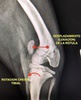

LUXACIÓN DE ROTULA ( L.R.)

La LR es una de las enfermedades más comunes de la rodilla canina, especialmente en razas enanas y pequeñas

¿QUÉ ES LA LUXACIÓN DE ROTULA?

La rótula ( un hueso incluido dentro del tendón más grande de la extremidad posterior, el tendón del cuádriceps) está en condiciones normales “encajado” entre dos paredes verticales de hueso ( las crestas trocleares del fémur), que permiten el movimiento de arriba abajo ( el que se produce cuando el animal flexiona y